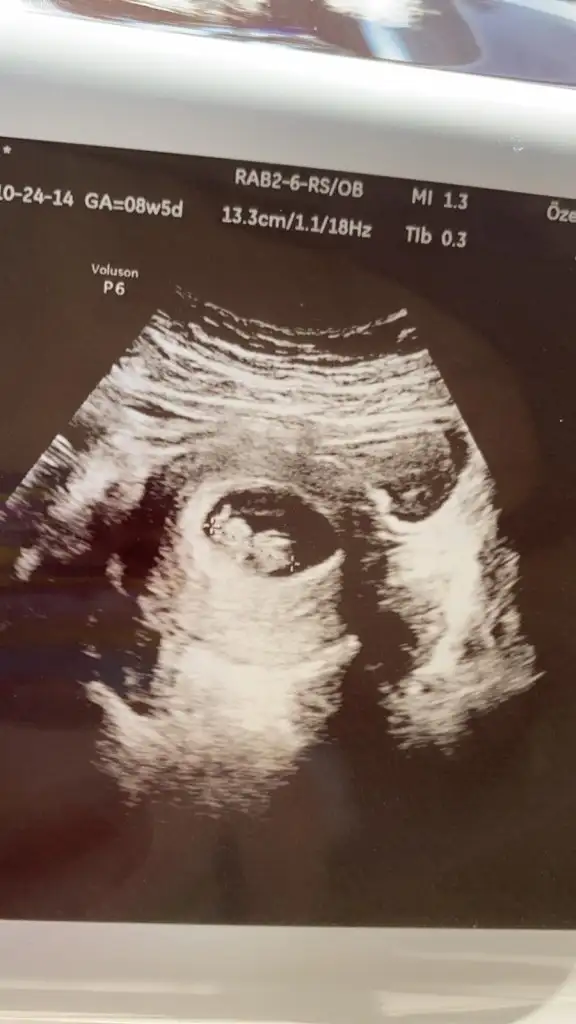

8+5 yazıyor uygun değil nub içinEki Görüntüle 2721344 10 haftalik usg yegenimin bi balar misiniz

Kız gibi sanki emin olamadım başka USG varsa paylaşınİkra meyra banada bakarmısınız12 haftalık resmi

Kız gibi sanki emin olamadım başka USG varsa paylaşınIkra meyra 13 hafta

Kız gibi sanki emin olamadım başka USG varsa paylaşın

Net degil